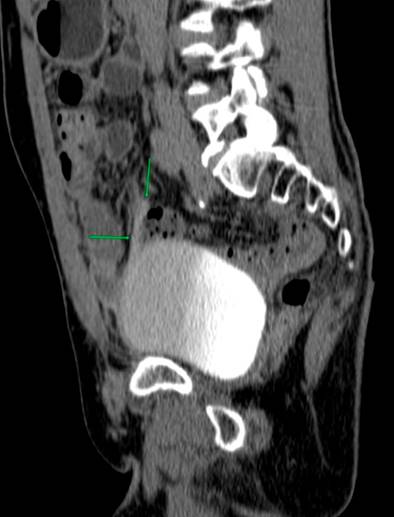

Due to the recurrence of the symptoms, chronicity, absence of etiology after a detailed study, and taking into account the patient’s surgical history, less frequent etiologies were considered a possibility of uroperitoneum. Creatinine was measured in the peritoneal fluid, the result of which was 7.44 mg/dL, and the gradient between fluid and serum was 5.74, which further increased the suspicion. Due to the uncertainty in the face of acute kidney injury and suspicion of urinary fistula, the nephrology service requested a voiding cystography with dynamic films, finding a bladder dome defect with active contrast extravasation into the peritoneal cavity, which confirmed the presence of uroperitoneum and explained the elevation of nitrogenous gases that simulated acute renal injury (Figure 1). To better characterize the genitourinary tract lesion and surgical planning, a urotomography was performed (Figure 2) with evidence of a defect in the bladder dome of 7.8 mm towards the right side in its anterior portion, with evidence of extraluminization of the contrast medium as a sign of rupture. After this characterization, he was scheduled for laparotomy with cystorrhaphy, performed at another institution.